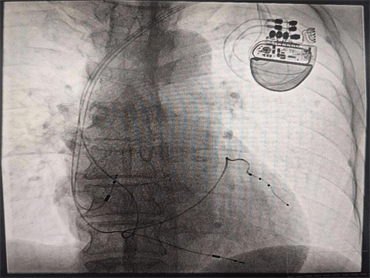

由于患者心功能差,身材消瘦,且情緒較為焦慮,術(shù)后易伴并發(fā)癥,心血管內(nèi)科九病區(qū)醫(yī)療團隊針對該患者的情況進行術(shù)前討論研究,護理團隊采用敘事護理的方法解除了患者的焦慮情緒,在充分考量患者的個體因素后,經(jīng)患者及家人同意,確定手術(shù)方案。術(shù)中,崔主任親切的語言緩解了張大爺?shù)慕箲],在平靜的狀態(tài)下成功將三個電極植入到右心房、右心室、左心室(冠狀靜脈分支遠端)圓滿完成了手術(shù)。術(shù)后,反復(fù)程控參數(shù),達到起搏器工作狀態(tài)最優(yōu)化,復(fù)查心電圖示QRS波恢復(fù)到107ms,明顯變窄,患者心臟功能及癥狀較手術(shù)前顯著改善,遠期療效在進一步觀察中,將通過不斷程控,優(yōu)化心臟起搏器參數(shù),達到更好的治療效果,崔主任親自為患者按時換藥,術(shù)后切口愈合良好。通過護士長魏薇及護理團隊的精心指導(dǎo),張大爺術(shù)后的康復(fù)鍛煉也非常順利。

心臟再同步化治療(CRT或者CRT-P)是近年來發(fā)展迅速的治療心力衰竭患者的重要手段,它是將電極植入右心房、右心室及左心室三腔起搏,使左右心室同步激動,同步收縮,改善心臟功能,降低心力衰竭患者病死率,是心力衰竭者的新希望,是心力衰竭治療史上一個里程碑的突破。